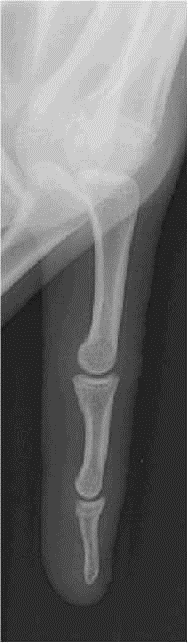

LES DOIGTS

PROFIL

TECHNOLOGIE

– – Identique à celle de la main

CRITERES DE REUSSITE

– – Voir les 3 phalanges

IMAGE NORMALE